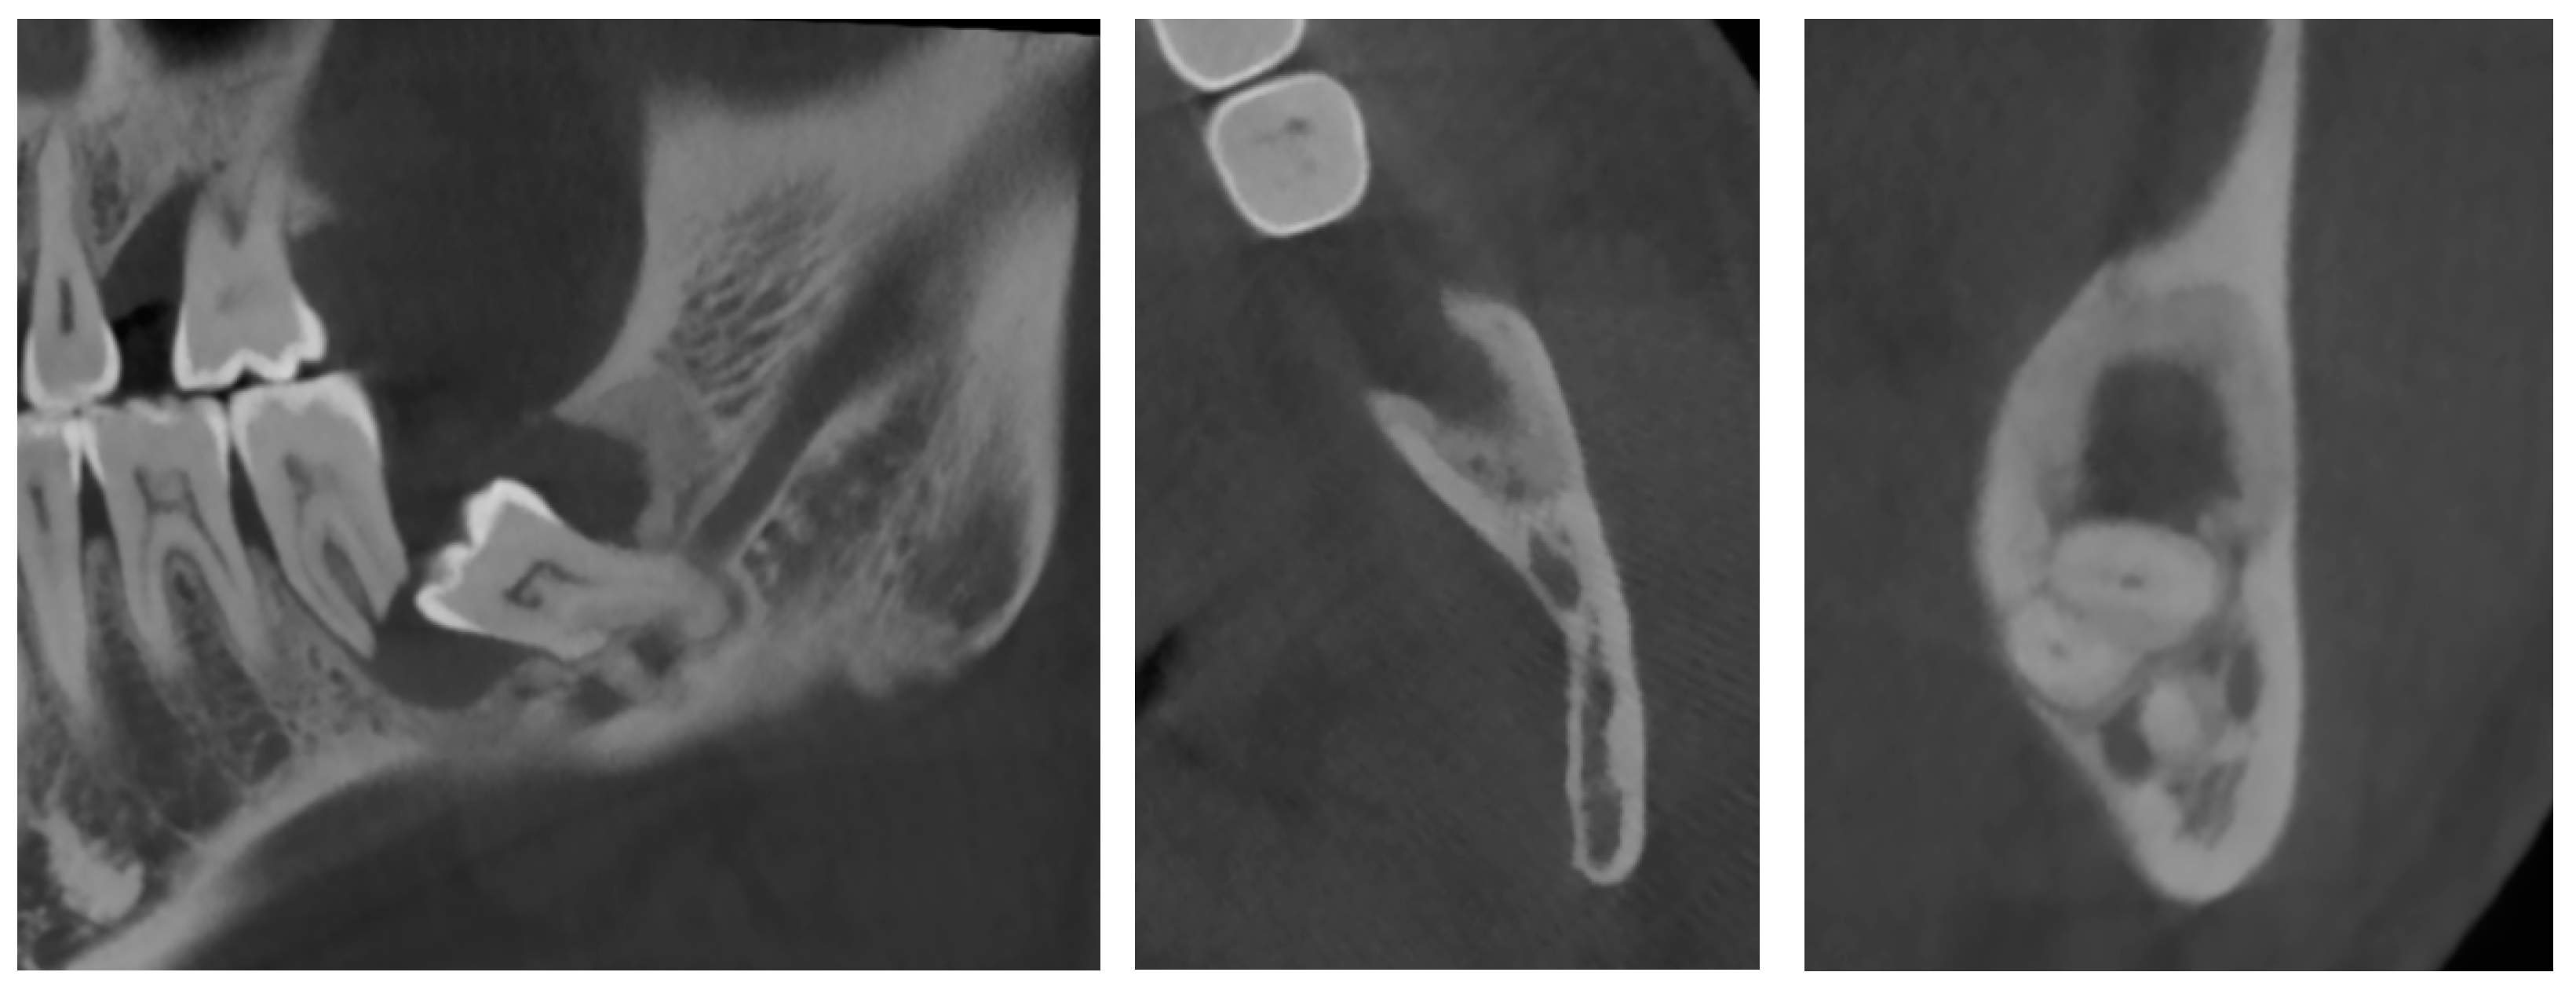

A 38-year-old female in good general health was referred by her orthodontist for diagnosis and treatment of a lesion in the right lower quadrant of the mandible discovered incidentally on an OPG X-ray performed prior to orthodontic treatment. The oral examination was unremarkable, and the patient was asymptomatic.

A new OPG X-ray revealed the presence of a pericoronal radiolucent lesion on an impacted tooth #48, which was inverted in the mesio-caudal direction (Figure 5). The lesion was well defined, measured 13 × 15 mm, and was surrounded by a thin sclerotic border overlapping with the distal root of tooth #47, which appeared slightly resorbed. The cyst also overlapped with the IAC, whose walls could not have been well-identified during this exam. The presumptive diagnosis was a DC.

On the complementary CBCT X-ray, it was observed an impacted tooth #48 in horizontal/inverted orientation in the mesio-caudal direction (Figure 6). The two roots were not in direct contact with the right IAC, and the tooth crown did not come into direct contact with the root of tooth #47. The pericoronal space was markedly enlarged, 13 mm wide, 17 mm high, and 15 mm long, compatible with a DC. The visible resorption of the distal root of tooth 47 made a differential diagnosis of odontogenic keratocyst less likely. The lesion was associated with an alveolar crest dehiscence of over 4 mm in length and thinned lingual cortex. The lesion displaced the IAC caudally, causing loss of visibility of its wall.